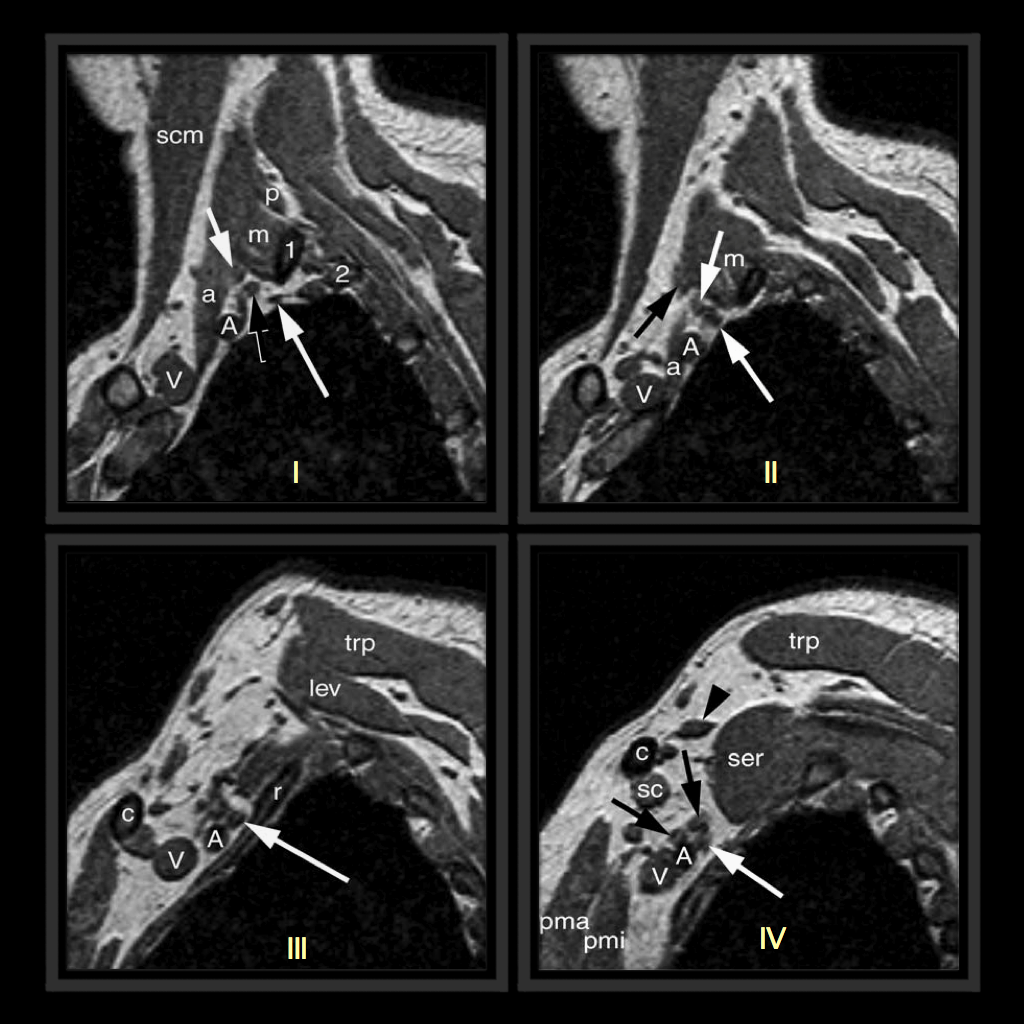

From limpeter-mriblog.blogspot.com

MRI BLOG Brachial Plexus MRI (I/II) What Is A Mri Brachial Plexus Magnetic resonance imaging (mri) is the imaging modality of choice for the evaluation of the brachial plexus due to its. Evaluation of brachial plexus disease typically begins with obtaining the patient history and performing a physical examination and electrophysiologic testing. This article discusses mr imaging evaluation of the brachial plexus, relevant anatomy, and common pathology with clinical and imaging details,. What Is A Mri Brachial Plexus.